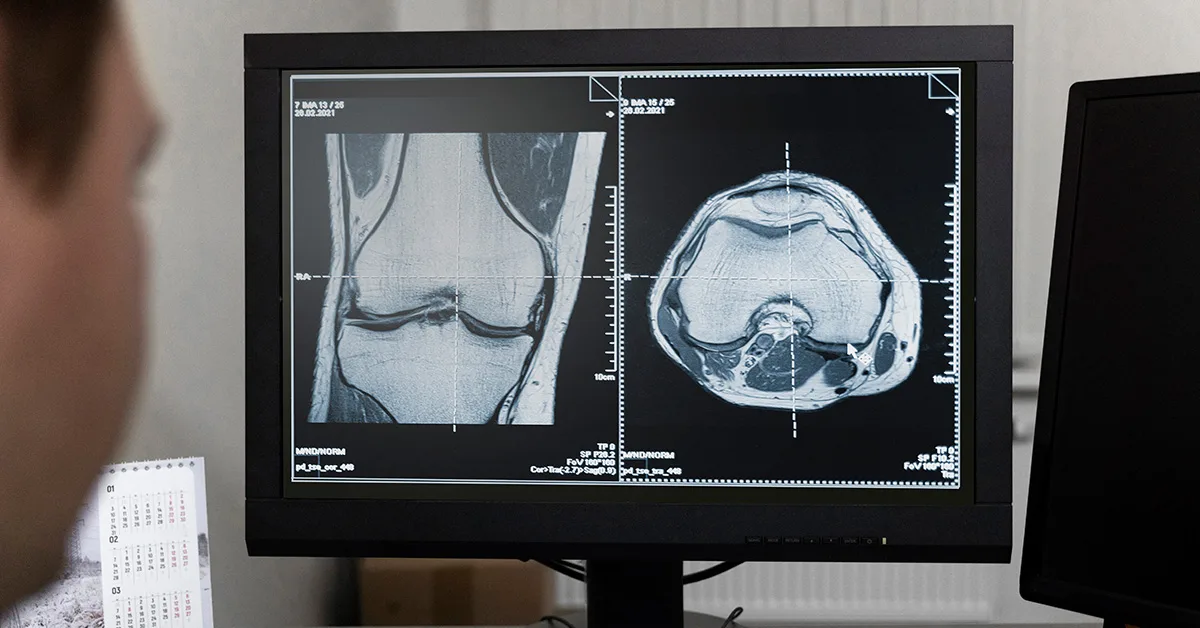

A radiologia especializada refere-se ao estudo e prática da radiologia focada em áreas específicas do corpo humano ou em técnicas particulares de imagem.

Enquanto a radiologia em geral envolve o uso de radiação para diagnosticar e, em alguns casos, tratar doenças, a radiologia especializada aprofunda-se em determinadas regiões anatômicas ou patologias.

Outras subespecialidades incluem Radiologia Musculoesquelética, Radiologia Torácica, Radiologia Mamária, Radiologia Pediátrica, entre outras.

- Diagnóstico por imagem músculo esquelético;